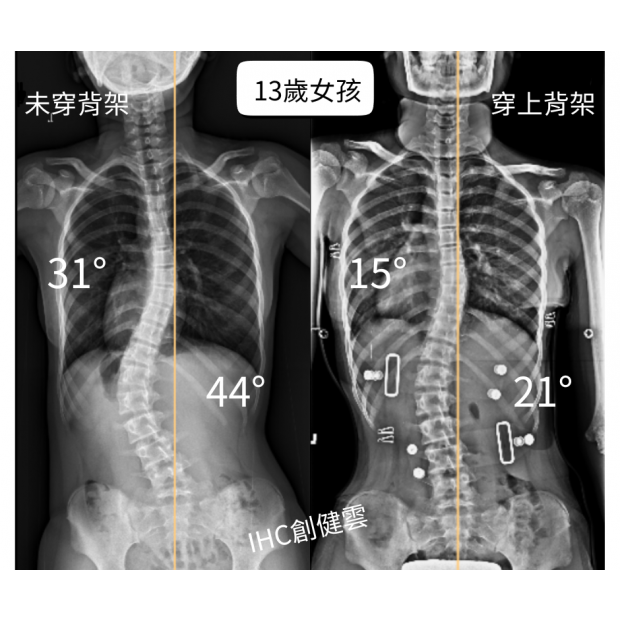

13歲脊椎側彎女孩,胸彎31度腰彎44度

原本在台大醫院就診,後醫師轉介,訂製【施羅斯側彎矯正背架】。

在專業評估與客製化設計完成後,背架的立即矯正效果:

胸彎由31度→15度,腰彎由44度→21度!

在背架支撐下,整體身形也呈現 更筆直、體態更平衡的狀態。